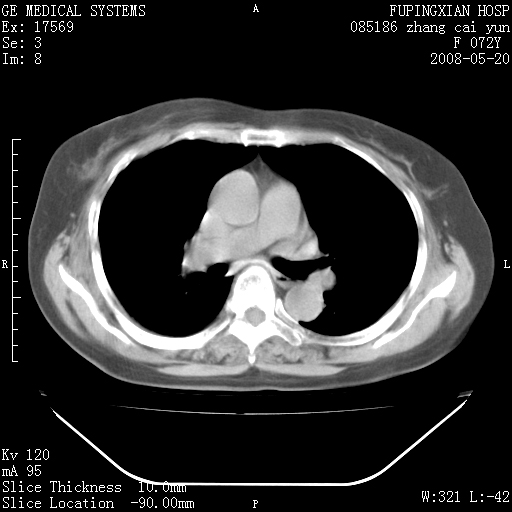

标题: CT13542:发热,咳嗽数日,经抗菌素治疗好转,请大家看排除 [打印本页]

标题: CT13542:发热,咳嗽数日,经抗菌素治疗好转,请大家看排除

上叶支气管略变窄并通畅,内壁光滑。考虑:单纯阻塞性肺炎!

右上叶支气管走行自然,未见明显管壁增厚等征像,另左主支气管起始部可见异常腔道向左侧延展左肺动脉干后方,与左下叶支气管相通,为左下叶支气管变异?

有节段性阻塞性肺炎与不张,近段支气管狭窄,周围散在肿大淋巴结影,以周围型肺癌可能性大,建议纤支镜检查。

右肺上叶实变影,内见支气管充气征,右上叶支气管通畅,肺门区未见软组织密度影,抗炎治疗有效,考虑炎症,建议继续抗炎治疗复查。

右上肺实变,间内有支气管充气征,考虑炎症,建议抗炎后复查